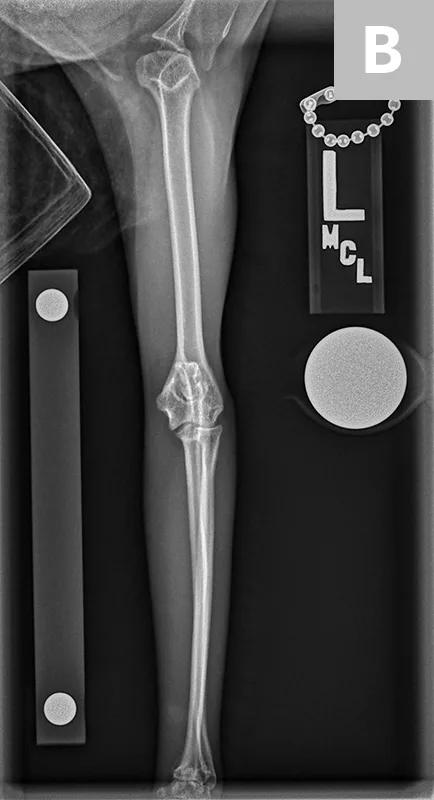

FIGURE 3

Lateral (A) and dorsoventral (B) views of the pelvis. Figure A shows a moderate amount of the smoothly marginated, bridging, bony proliferations surrounding the 2nd through 5th coccygeal vertebrae. A moderate amount of kyphosis is present on the tail, centered in the bony proliferation. A mild amount of irregularly marginated bony proliferation is present surrounding the facet joint of the C5-C6 intervertebral disk space. Figure B shows poor coverage of the right femoral head by the acetabulum. A moderate amount of irregularly marginated bony proliferation is present on the cranial and caudal aspects of the acetabulum and femoral neck. There is decreased soft tissue associated with the left pelvic limb as compared with the right. A small osteophyte on the left cranial acetabulum can be noted. Image courtesy of Dr. Karen Perry. Interpretation: Chronic, healed caudal vertebral fracture, C2-C4. Moderate, right coxofemoral osteoarthritis and mild left coxofemoral osteoarthritis